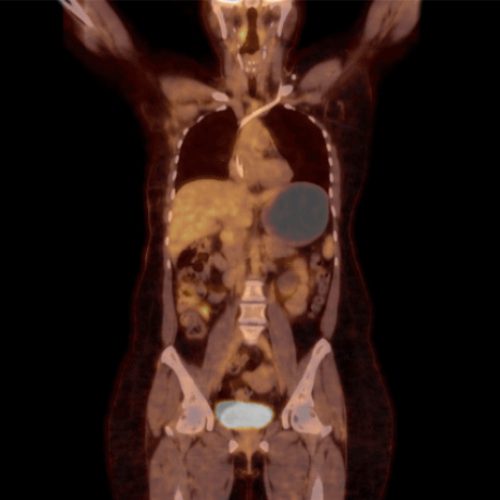

Ejemplos de imágenes del PET-CT mostrando ubicaciones de los órganos y FDG acumulado.

La tomografía PET detecta en dónde se ha acumulado el FDG en el cuerpo. Por lo tanto, el estudio detecta la ubicación del cáncer metastásico.

• El cáncer metastásico está formado de células hipermetabólicas.

• Las células hipermetabólicas usan más azúcar (glucosa) que las células normales.

• La glucosa radioactiva (FDG) es inyectada de forma intravenosa.

• Durante el periodo de relajación, el FDG se acumula en las células hipermetabólicas.

• La mesa mueve al paciente a través del escáner TC (5 min).

• La mesa mueve al paciente a través del detector de FDG (15 min).